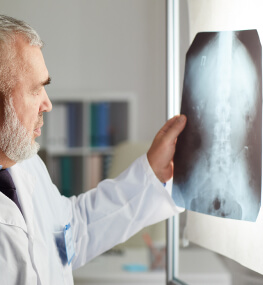

На прийомі травматолог детально вислуховує про те, що вас турбує, дізнається симптоми і скарги. Після чого огляне вас і призначить подальшу процедуру обстеження, якщо в цьому є необхідність. Далі буде проведена діагностика і лікування до повного одужання пацієнта.

Ми володіємо сучасним обладнанням за допомогою якого можна швидко і якісно діагностувати патологію. На сайті надані фото наших апаратів і кабінетів, тому ви можете переконатися у високому рівні нашої роботи.

У нас є такі методи діагностики:

- КТ;

- Артроскопія суглоба;

- МРТ;

- Ультразвукове дослідження;

- Цифрова рентгенографія;

- Лабораторні методи діагностики.